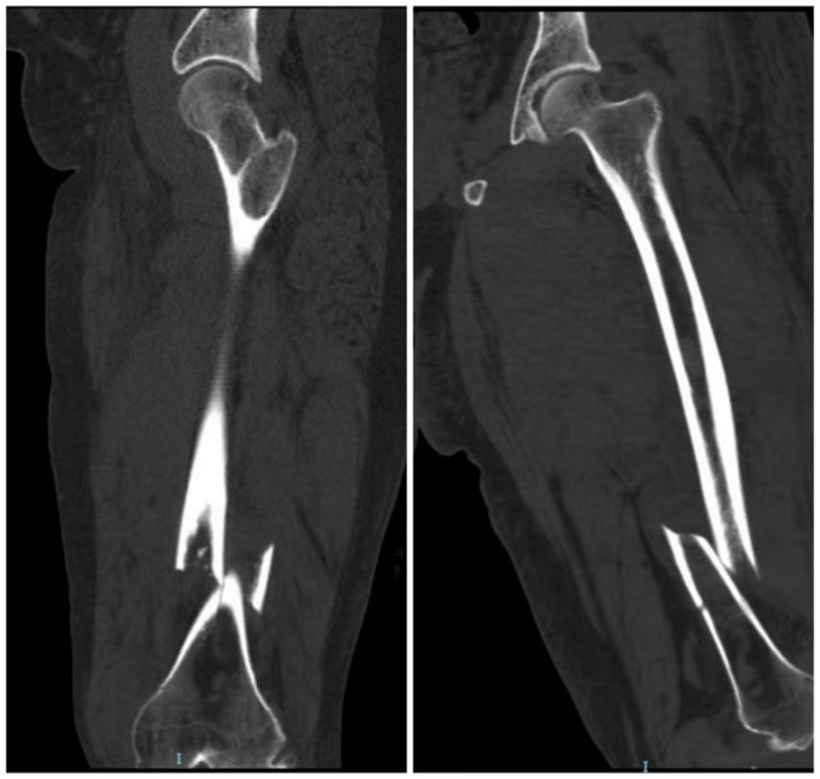

图中所示为患者的术前影像。

入院后,医护人员第一时间完善各项相关检查,明确诊断为左股骨干骨折、膝关节血友病性关节病,且其为既往血友病A型患者。据介绍,血友病是一种X染色体连锁的隐性遗传性出血性疾病,因凝血因子Ⅷ或Ⅸ基因缺陷,导致患者终身凝血功能异常;其中血友病A占比达80%~85%,患者以男性为主,核心临床表现为自发性出血或轻微损伤后出血不止,反复出血还可能引发关节病变、肢体残疾等严重并发症。而李先生此次所患的股骨干骨折,属于高能量损伤导致的不稳定骨折,保守治疗无法维持下肢骨骼的对位对线,虽具备明确的手术指征,但血友病带来的凝血功能障碍,让这场手术成为临床诊疗中名副其实的“禁区手术”。

据了解,股骨干骨折占成人骨折的2.2%,多由强大外力冲击所致,骨折部位常伴随粉碎、移位,且周围筋膜、肌肉易受损伤,急性期出血量可达1000-2000毫升,因此不稳定股骨干骨折需尽早复位固定。对于血友病患者而言,合并此类骨折后诊疗难度大幅提升——不仅要攻克骨折本身的救治难题,更要应对凝血功能异常带来的高出血风险。术前需在血液内科专业支持下精准补充凝血因子,术中需实施精细化操作减少出血,术后需严密监测凝血功能、防范出血并发症,这对医院的多学科协作能力和临床诊疗水平提出了极高要求。